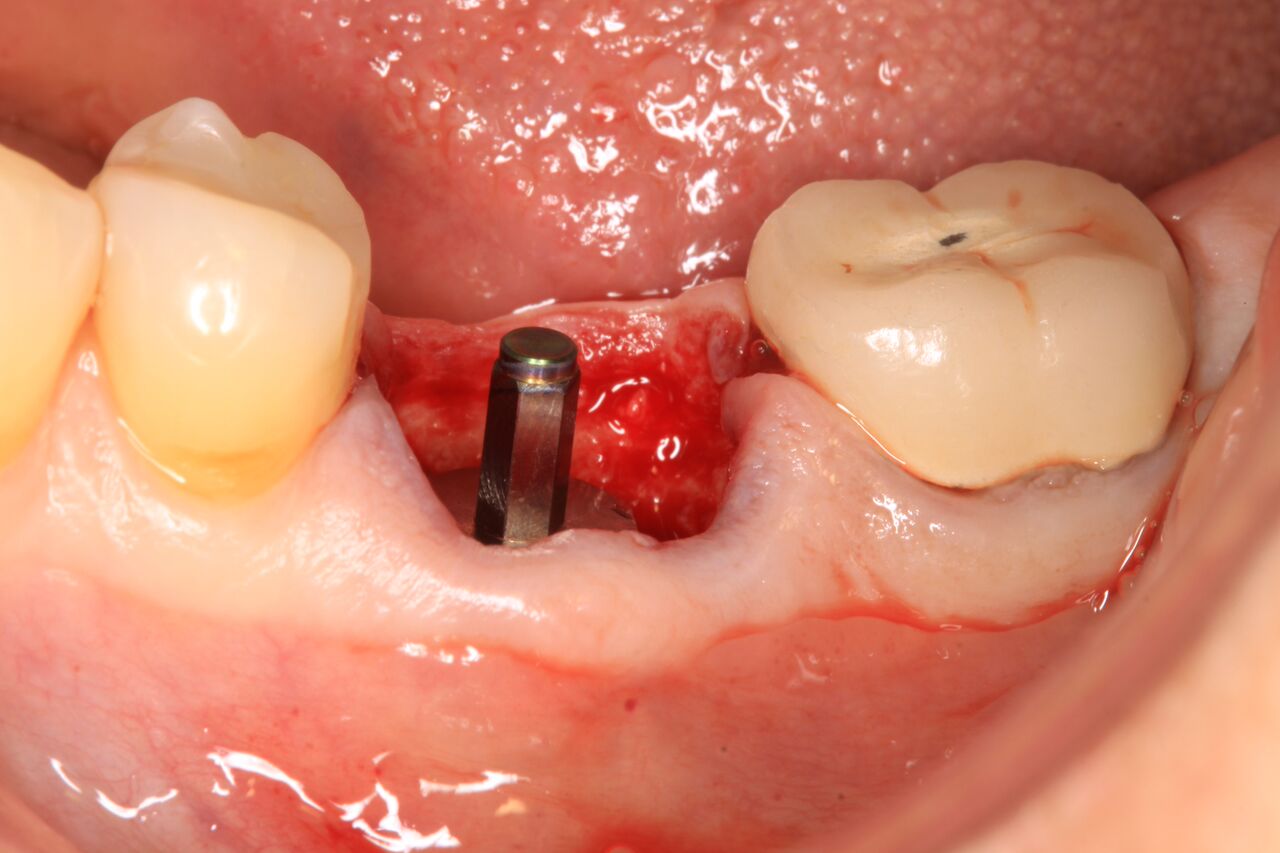

(10.) Initial clinical evaluation of Nos. 12 through 14 after crown on No. 12 and pontic on No. 13 removed.

Figure 10

(11.) Extraction of fractured and decayed No. 12 with periapical granuloma and original

Figure 11

(12.) Extraction of fractured and decayed No. 12 with periapical granuloma and original

Figure 12

A 67-year-old woman presented on an emergency basis with a bad odor and taste from crown No. 12, which had been diagnosed that day at hygiene recall as decayed and no longer attached to the underlying root (Figure 8 and Figure 9). The patient was anesthetized and the existing bridge was sectioned (Figure 10), leaving crown No. 14 intact. The No. 12 root was extracted and the site was fully debrided of granuloma. A platform shift implant was stabilized in excess of 45 Ncm in position No. 12, which was prosthetically correct. The soft tissue of pontic site No. 13 was contoured to mimic soft tissue contours of a bicuspid and an implant was secured in excess of 45 Ncm. Implant No. 13 was milled to allow for unimpeded seating of the temporization abutment, whereas implant No. 12 did not need milling as it was a platform-shift implant. The existing crown No. 12 and cantilever No. 13 were revised to be a temporary bridge on Nos. 12 and 13 (Figure 11 and Figure 12). The revised temporary bridge was positioned in infraocclusion and cemented after the extrusion of excess cement extraorally (Figure 13). No bone graft or sutures were placed as the temporary crowns sealed the sockets.